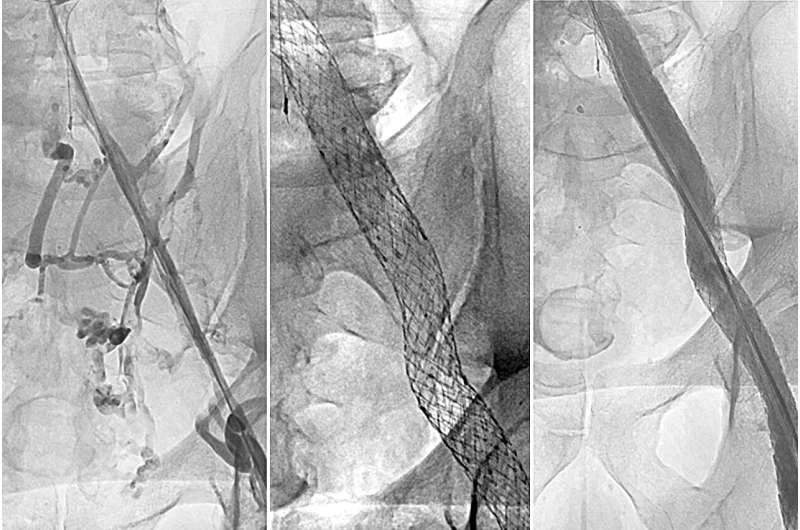

Ken Checicki: How Restoring Blood Flow Can Solve Post – DVT Complications

“Ken’s Notes: Opening a narrowed vein damaged by deep vein thrombosis can effectively treat an often painful complication following a blood clot.”